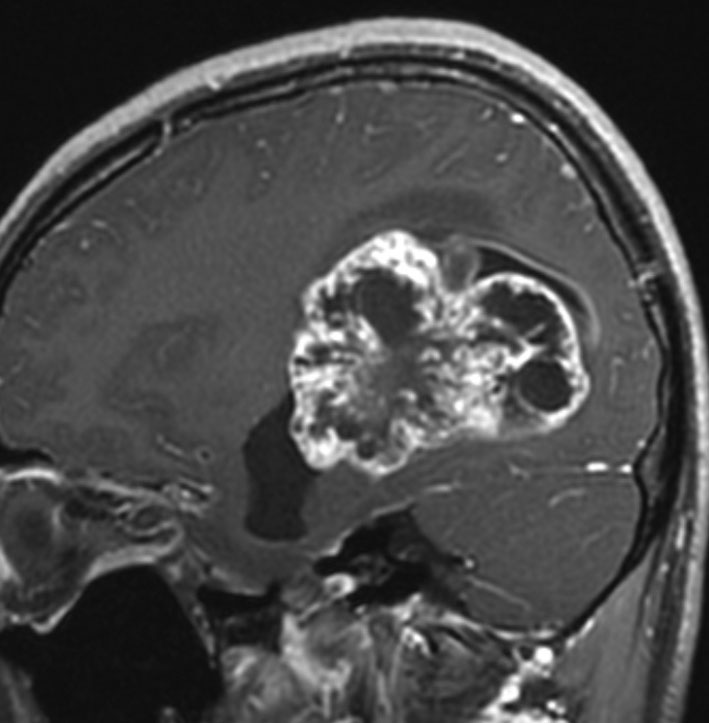

テント上 退形成性上衣腫 グレード3:EPN-ST-RELA negative

膠芽腫を思わせるような,腫瘍内部の壊死,のう胞形成,出血があります。高度の血管増生と動静脈シャントがあり,早期腫瘍静脈描出 early venous fillingがみられます。10代のおそらく右側脳室三角部辺りから発生した退形成性上衣腫です。激しい出血がありましたが全摘出 gross total removal しました。リスクをかえりみない手術も必要です。画像所見も病理組織像も超悪性腫瘍なのですが,治る可能性があるタイプです。